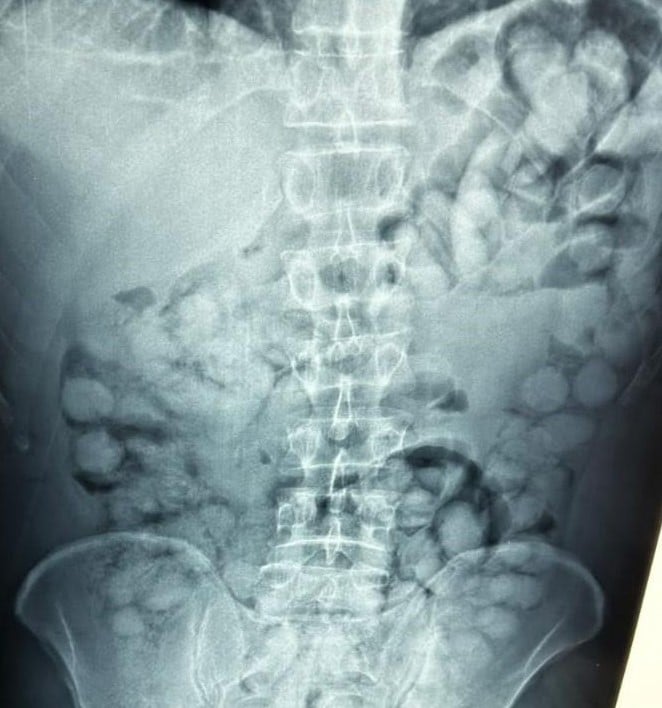

Μάλιστα όπως βλέπουμε σε σχετικές φωτογραφίες, ο εντοπισμός της κοκαΐνης έγινε με χρήση ακτινογραφίας στο σώμα του 37χρονου Βραζιλιάνου dealer.

Πιο αναλυτικά, ο κατηγορούμενος, αφιχθείς αεροπορικώς από το εξωτερικό, διαπιστώθηκε ότι είχε προβεί στην κατάποση 100 αυτοσχέδιων ωοειδών συσκευασιών, αεροστεγώς περιτυλιγμένες με νάιλον ταινία, που περιείχαν κοκαΐνη συνολικού μικτού βάρους 1.120 γραμμαρίων.